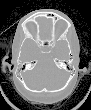

1. ได้ภาพที่ละเอียดชัดเจน แยกความทึบของเนื้อเยื่อต่าง ๆ ในร่างกายได้ละเอียดมาก เช่น แยกเนื้อเยื่อสมองออกเป็นส่วน แยก

ความทึบของก้อนต่าง ๆ ว่าเป็นก้อน(solid) ถุงน้ำ หรือมีหินปูนอยู่หรือไม่ ซึ่งเครื่องเอกซเรย์ธรรมดาไม่สามารถทำได้ นอกจากนี้

ยังสามารถบอกขนาด ตำแหน่งของส่วนที่ผิดปกติ ตลอดจนการกระจายของโรคได้ 2. สามารถแยกอวัยวะต่าง ๆแต่ละส่วนไม่ให้มีการซ้อนกัน เช่น สามารถเห็นเนื้อสมอง และโพรงสมองแยกจากกัน 3. นอกจากใช้ในด้านการวินิจฉัยโรคแล้วยังช่วยในด้านการรักษาผู้ป่วยด้วย เช่น ช่วยในการเจาะถุงน้ำ หนอง ฝี หรือผ่าตัดสมอง บางส่วน 4. ช่วยคำนวณวางแผนการรักษาโดยรังสีรักษาในผู้ป่วยที่เป็นเนื้องอก โดยสามารถคำนวณภาพของก้อนเนื้องอกจริง ๆ 5. ปัจจุบันมีเครื่องเอกซเรย์คอมพิวเตอร์รุ่นใหม่ ๆ สามารถศึกษาการไหลเวียนของกระแสเลือด และการไหลเวียนของน้ำสมอง ไขสันหลังได้ โดยการฉีดสารทึบแสง(dynamic scan) ร่วมด้วย 6. การตรวจด้วยเอกซเรย์คอมพิวเตอร์ เป็นการลดความเจ็บปวดและอันตรายจากการตรวจพิเศษทางรังสีแบบอื่น ๆ เช่น การตรวจ ระบบหลอดเลือด (angiography) 7. ช่วยลดเวลาในการตรวจวินิจฉัย ซึ่งเป็นผลดีต่อผู้ป่วย และโรงพยาบาล โดยเฉพาะอย่างยิ่งเครื่องรุ่นใหม่ ๆ ยิ่งให้ประสิทธิภาพ ทั้งทางด้านเทคนิคการถ่ายภาพ และการแปลผลได้สูงขึ้น 8. ทางด้านเศรษฐกิจ แม้ว่าการตรวจด้วยเอกซเรย์คอมพิวเตอร์ จะมีราคาแพงแต่เป็นที่แน่ชัดว่า การตรวจด้วยวิธีนี้จะเป็นการช่วย ลดค่าใช้จ่ายในด้านการตรวจอื่น ๆ |